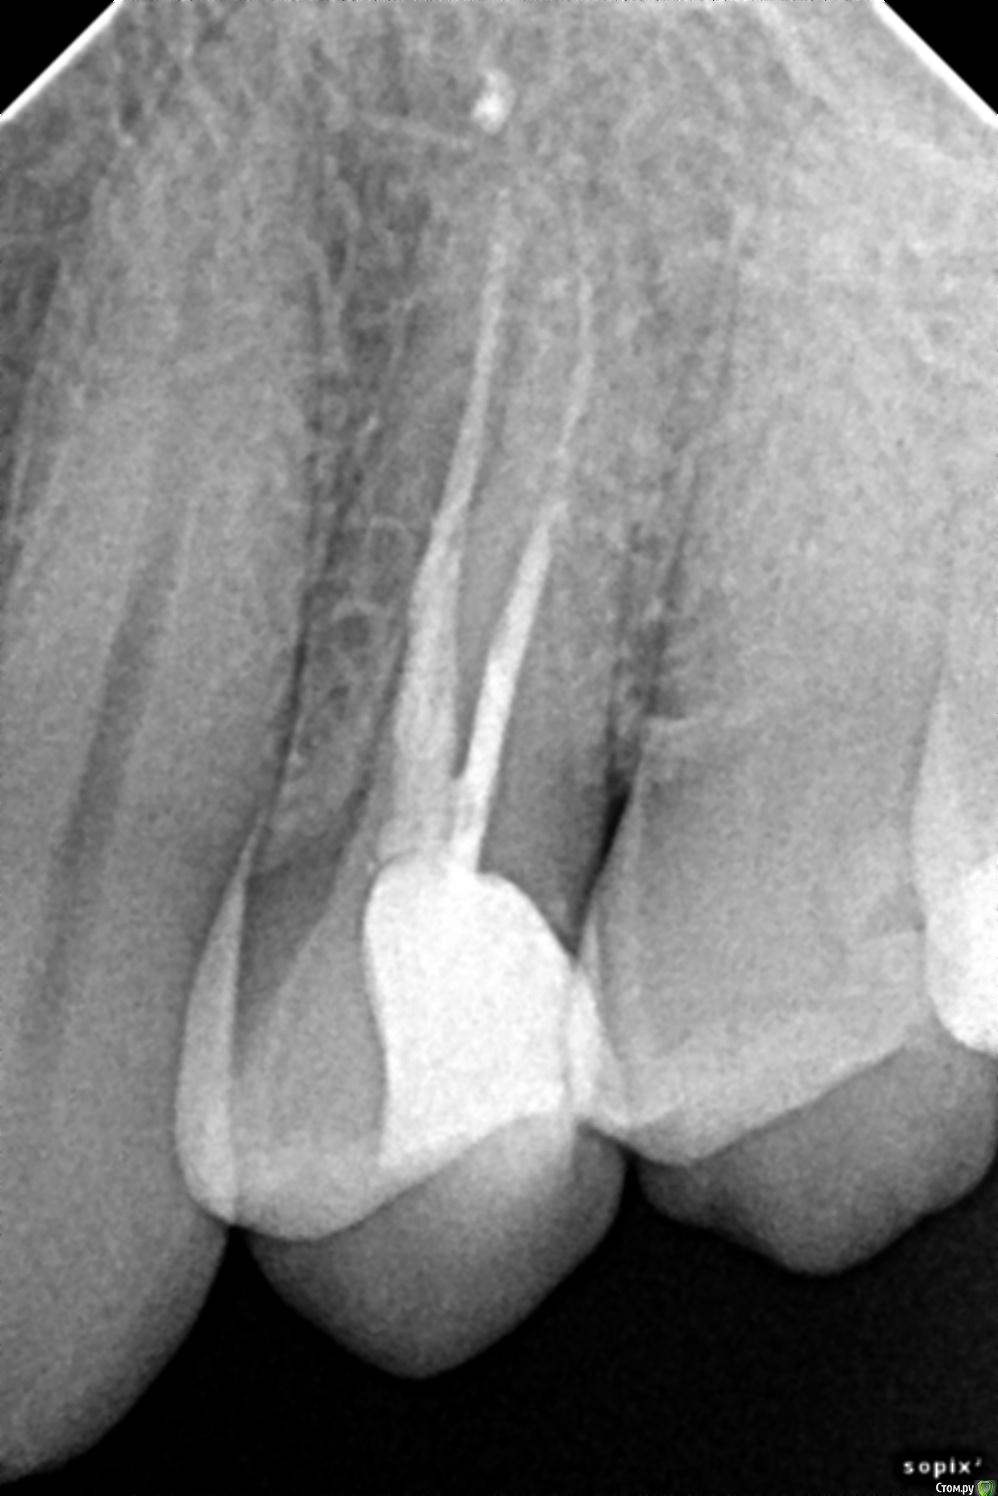

вдгиф Опубликовано 15 декабря, 2014 Поделиться Опубликовано 15 декабря, 2014 Здравствуйте,раскололся пополам зуб, стоит вопрос удалять или сохранять. Лечил 2 года назад.Посоветуйте, пожалуйста. Почему такое произошло, вроде на зубы особо не жалуюсь, всего 2 леченных в 37лет. Спасибо.Что теперь делать? 1 Ссылка на комментарий

вдгиф Опубликовано 15 декабря, 2014 Автор Поделиться Опубликовано 15 декабря, 2014 (изменено) Причина перелома в отсутствии протезирования. Зуб срочно удаляйте, возможно с непосредственной имплантациейА что значит отсутствие протезирования? Коронка? Почему на снимке один корень светлее- хорошо ли залечены каналы? Изменено 15 декабря, 2014 пользователем вдгиф Ссылка на комментарий

red_butler Опубликовано 15 декабря, 2014 Поделиться Опубликовано 15 декабря, 2014 А что значит отсутствие протезирования? Коронка? Почему на снимке один корень светлее- хорошо ли залечены каналы?Да, нужно было протезировать зуб искуственной коронкойНормально пролечены каналы, но это уже не важно 1 Ссылка на комментарий